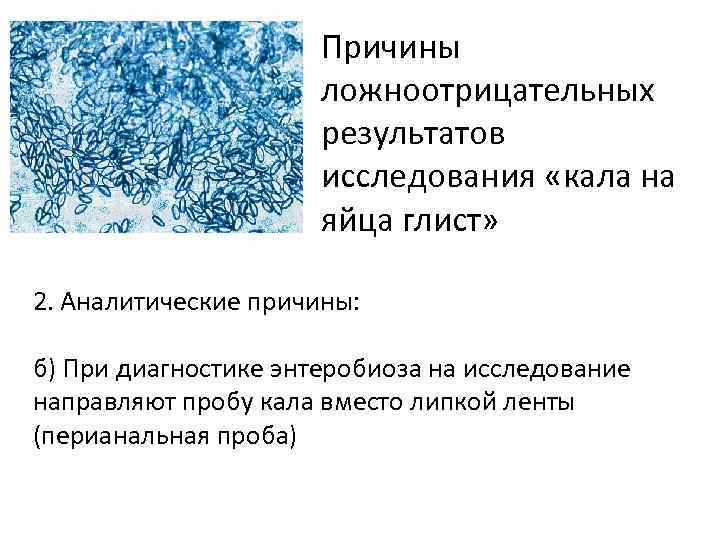

Причины ложноотрицательных результатов исследования «кала на яйца глист» 2. Аналитические причины: б) При диагностике энтеробиоза на исследование направляют пробу кала вместо липкой ленты (перианальная проба)